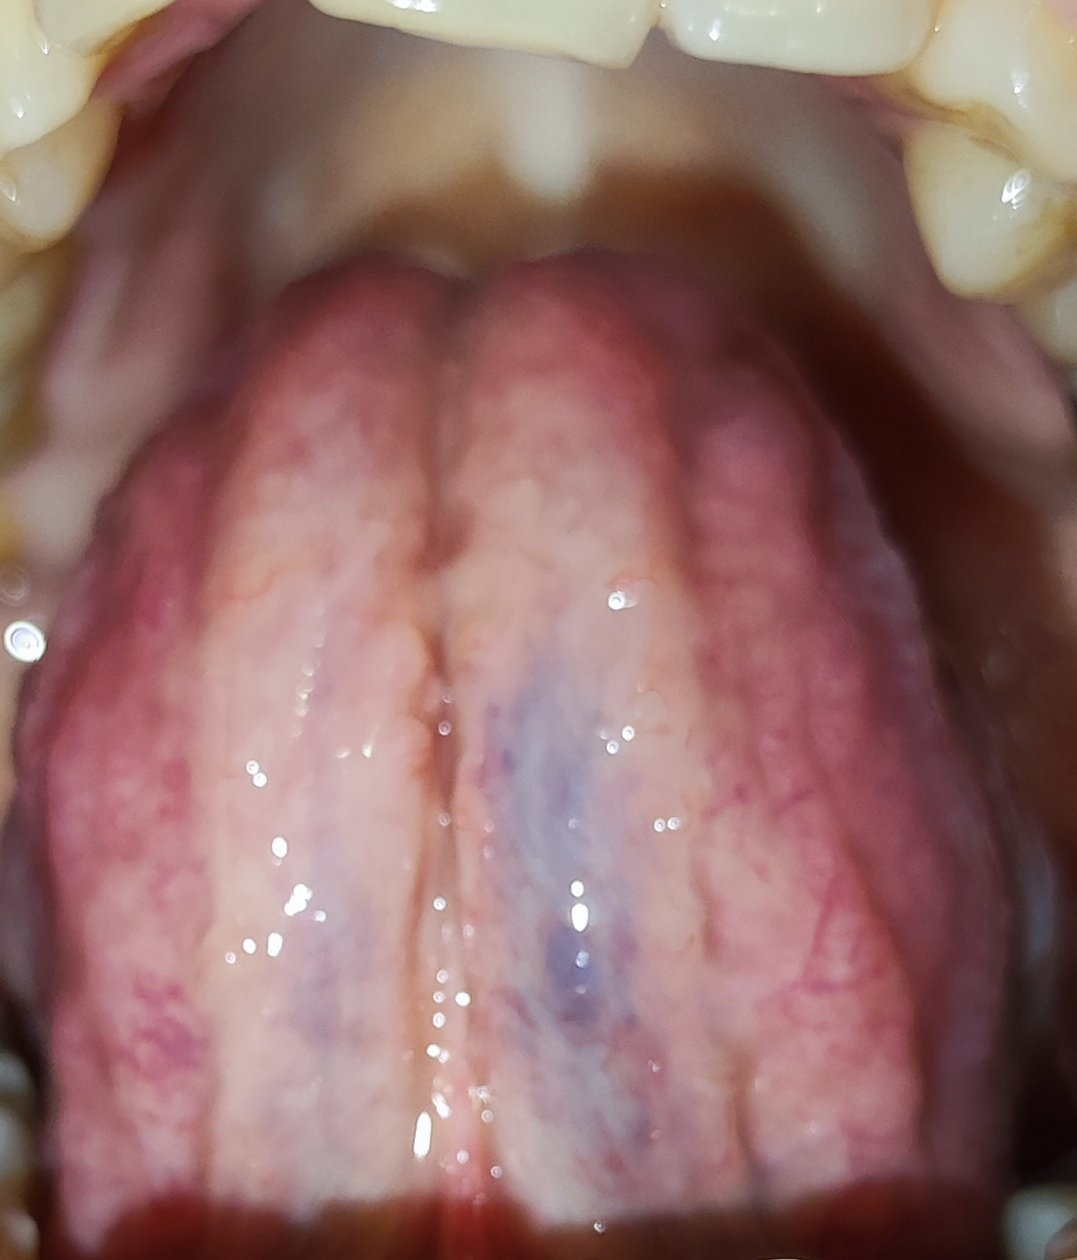

Dobrý deň. Dcéra 27 ročná má takýto jazyk,spodok jazyku je to v poriadku? Fialovo modrý.

Veď to sú normálne žily na jazyku...ty také nemáš?

Však to sú žily 😂